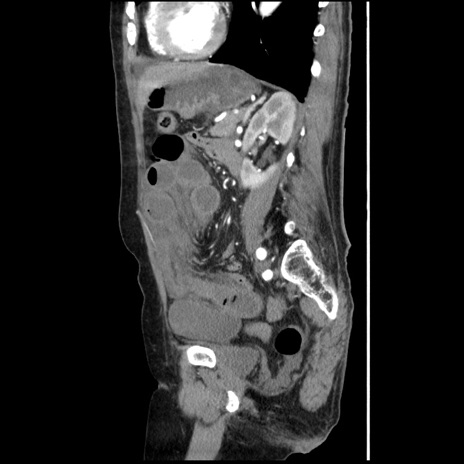

症例1(矢状断像)

【症例】80歳代女性

【主訴】腹痛

【現病歴】8時間前から腹痛あり来院。

【既往歴】糖尿病、脂質異常症、子宮体癌にて子宮全摘術

【身体所見】意識清明・会話良好だが腹痛で苦悶様、全腹部にわたって反跳痛と圧痛あり

【データ】WBC 13600、CRP 0.14、LDH 224、CK 90